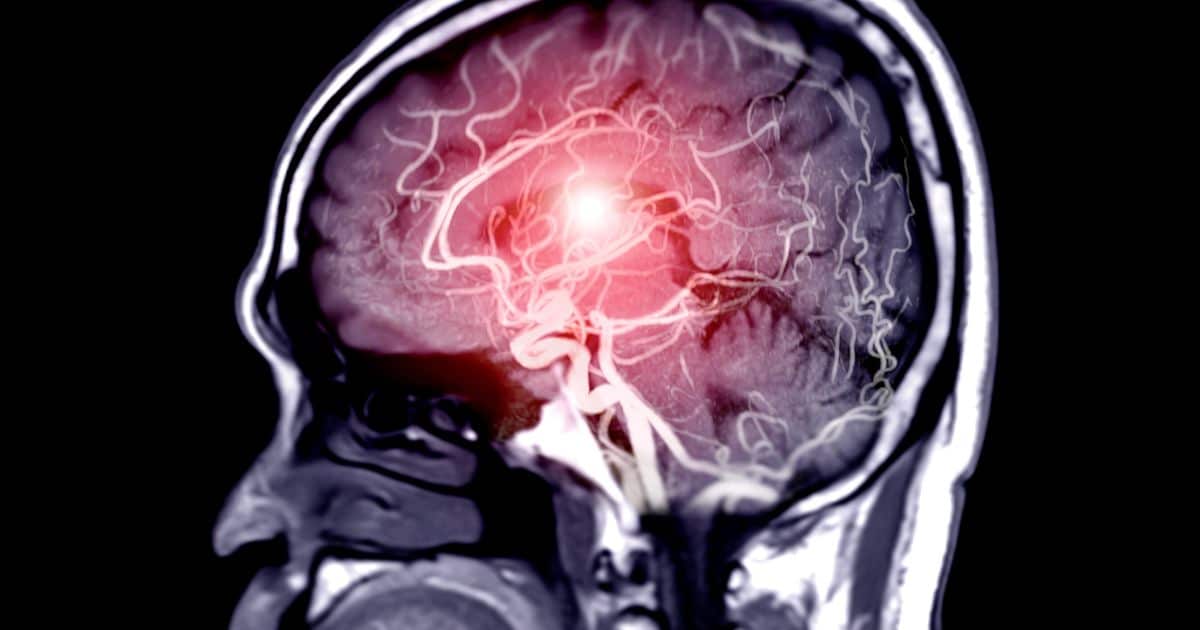

De acordo com especialistas, um acidente vascular cerebral (AVC) ocorre quando o suprimento de sangue para uma parte do cérebro é interrompido repentinamente. Com isso, podem ser comprometidos os movimentos, a fala ou o raciocínio da pessoa afetada pela condição – e a recuperação geralmente leva tempo.

O impacto varia de acordo com sua localização no cérebro e a extensão da área afetada, explica a Stroke Association. Desta forma, o AVC é uma emergência médica grave que requer atendimento hospitalar imediato, pois pode ser fatal.